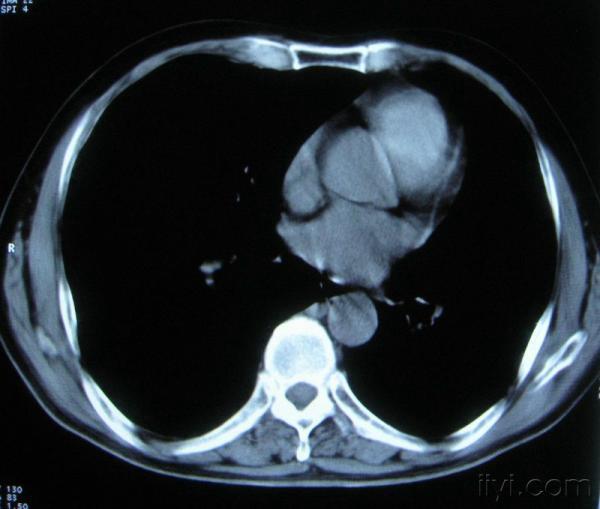

男。60岁,胸片示支气管炎治疗后复查CT。

你指那个肯定是淋巴结,中央系坏死,这很常见,特别在双侧腹股沟会经常看到。这个双侧腋窝及纵隔见多发小淋巴结征。

根据位置考虑应该是淋巴结,密度不均,是因为肿大的淋巴结中心液化坏死